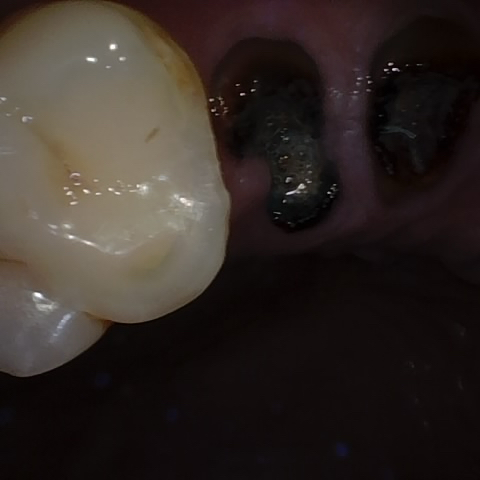

Annotated as "Good"